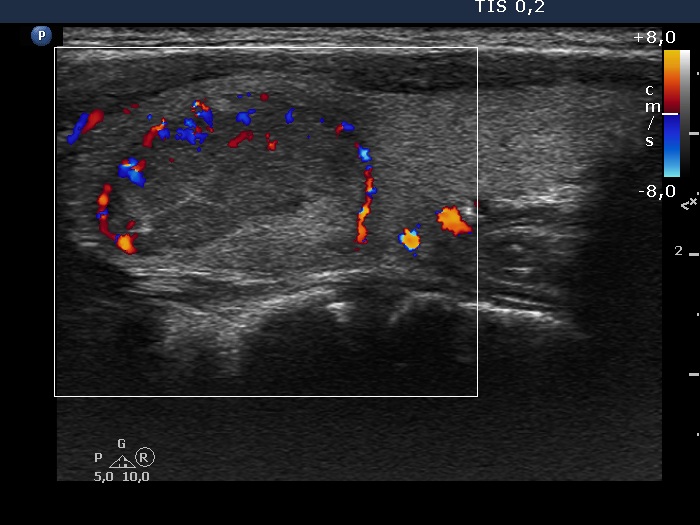

Left lobe, longitudinal scan, color Doppler mode. The lesion shows perinodular vascularization.